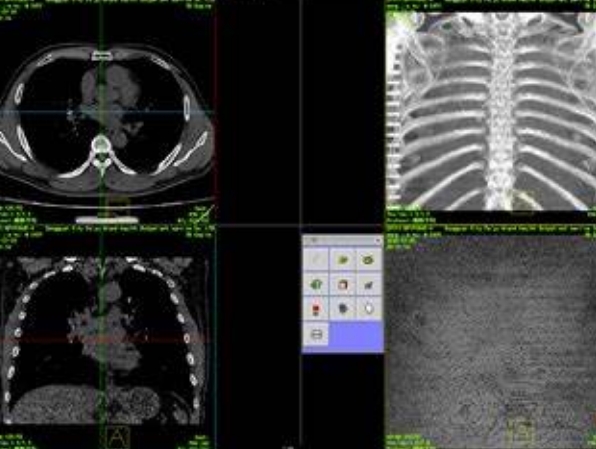

精準(zhǔn)手術(shù)導(dǎo)航的利器:術(shù)中三維影像重建系統(tǒng)提升外科手術(shù)精度

術(shù)中三維影像重建系統(tǒng)產(chǎn)品簡(jiǎn)介術(shù)中三維影像重建系統(tǒng)是一種先進(jìn)的醫(yī)療影像技術(shù),旨在通過三維重建技術(shù)為外科手術(shù)提供更加直觀、精確的影像支持…

骨科手術(shù)的得力伙伴:術(shù)中三維導(dǎo)航影像系統(tǒng)提升手術(shù)精度

術(shù)中三維導(dǎo)航影像系統(tǒng)產(chǎn)品簡(jiǎn)介術(shù)中三維導(dǎo)航影像系統(tǒng)是一種先進(jìn)的醫(yī)療設(shè)備,主要用于手術(shù)過程中實(shí)時(shí)提供高精度的三維影像導(dǎo)航。該系統(tǒng)結(jié)合了先…

高效骨科手術(shù)的新助手:術(shù)中三維導(dǎo)航影像系統(tǒng)的作用與優(yōu)勢(shì)

術(shù)中三維導(dǎo)航影像系統(tǒng)產(chǎn)品簡(jiǎn)介術(shù)中三維導(dǎo)航影像系統(tǒng)是一種先進(jìn)的醫(yī)療影像設(shè)備,主要用于在手術(shù)過程中提供實(shí)時(shí)的三維影像導(dǎo)航。該系統(tǒng)通過采集…

三維重建技術(shù)的革新:智能影像,精準(zhǔn)醫(yī)療的新篇章

三維重建技術(shù)的革新標(biāo)志著精準(zhǔn)醫(yī)療進(jìn)入了一個(gè)新的篇章。這項(xiàng)技術(shù)通過將二維的醫(yī)學(xué)影像數(shù)據(jù)轉(zhuǎn)換為三維模型,不僅提高了影像的直觀性和立體感,…